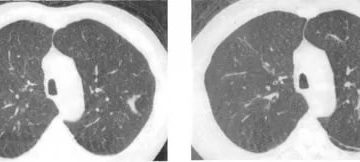

Киста легкого у взрослых: что это такое, симптомы, что делать и лечение При переводе с…

Пневмофиброз легких: что это такое, чем опасен и последствия, лечение народными средствами Пневмофиброз (пневмосклероз) –…